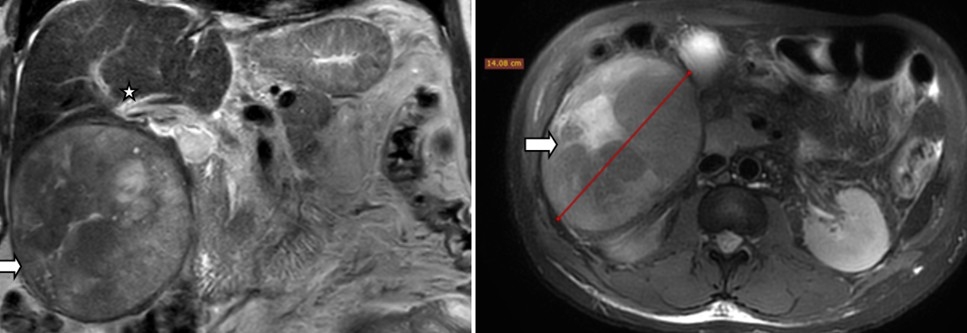

Observation : Patient de 57 ans avec hoquet persistant, ictère, hépatite virale B mal suivie. L’IRM abdominale (Fig1) a objectivé un volumineux CHC mesurant 14 cm de grand axe présentant un rehaussement typique wash-in, wash-out portal, selon les critères de l’EASL. Elle comprimait la branche porte droite refoulant le diaphragme et le rein droits. Ascite de faible abondance.

Figure 1 : IRM initiale en séquences coronale T2 SE (gauche) et axiale T2 FS (droite) présentant une volumineuse lésion du foie droit (flèche) comprimant la branche droite de la veine porte (étoile).